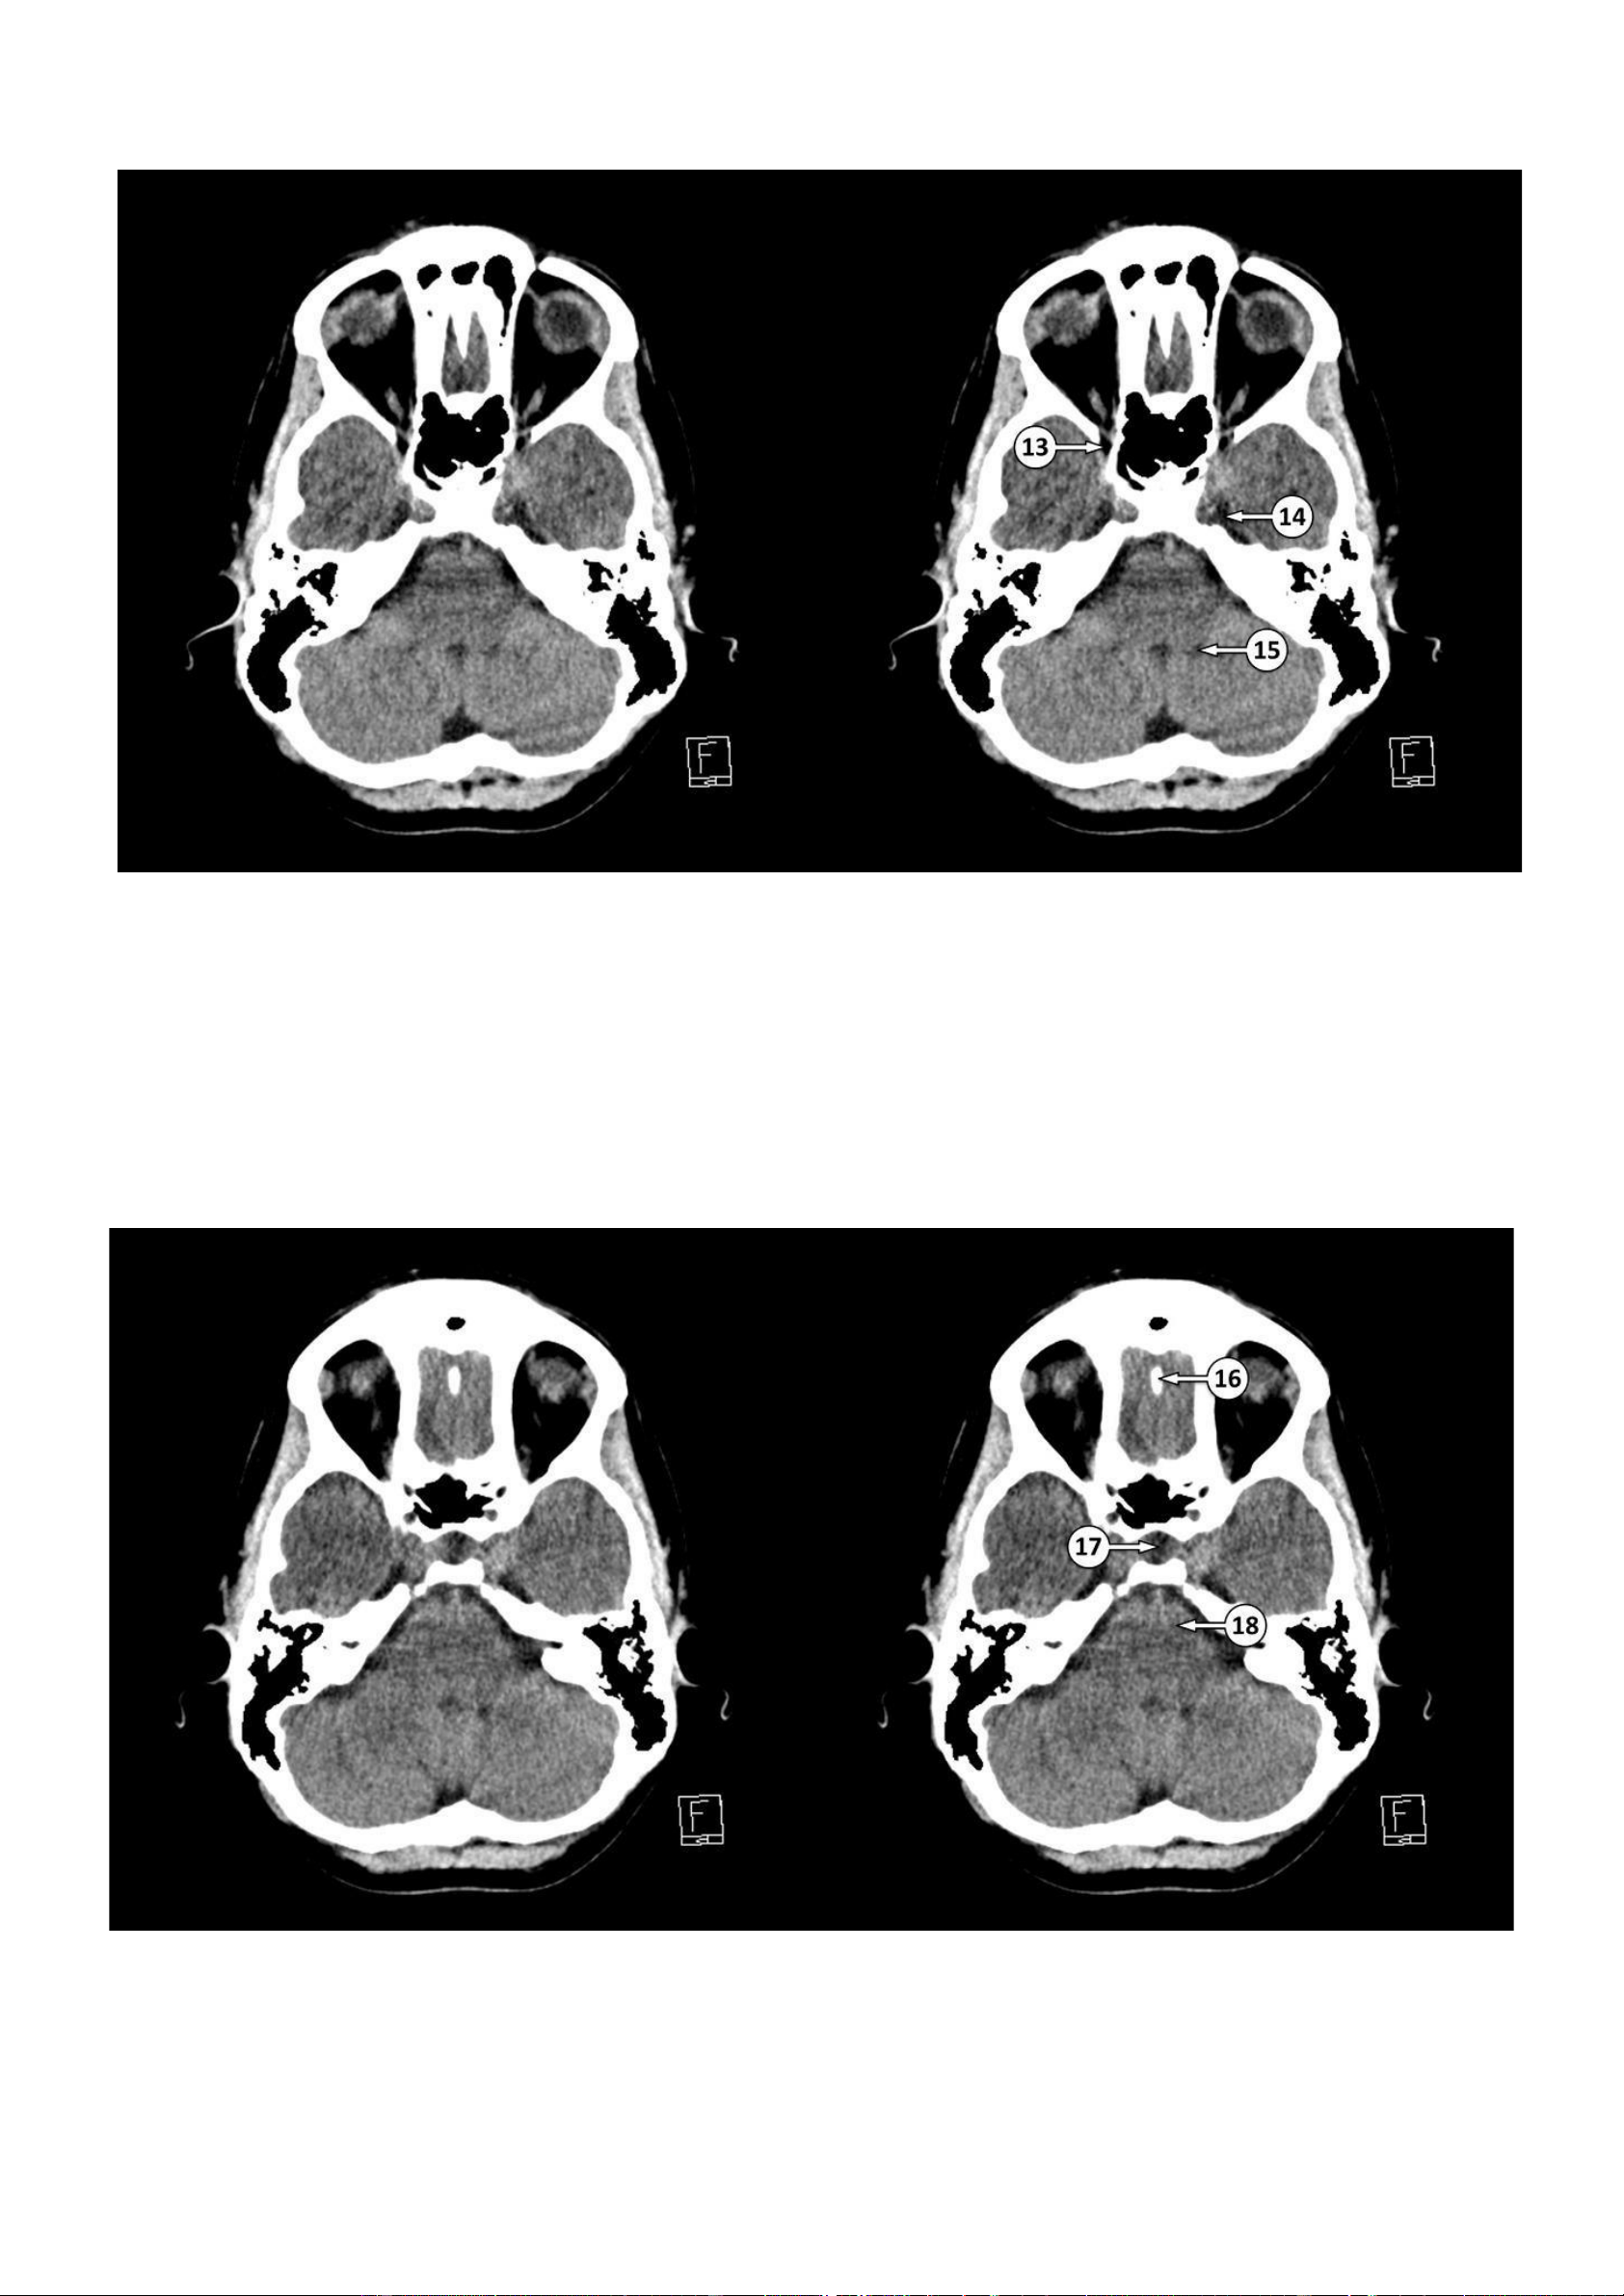

▪ Số 13: Khe trên ổ mắt ▪ Số 14: Hang Meckel ▪ Số 15: Lỗ Luschka 16: Mào gà 17: Hố yên 18: Cầu não lOMoAR cPSD| 22014077